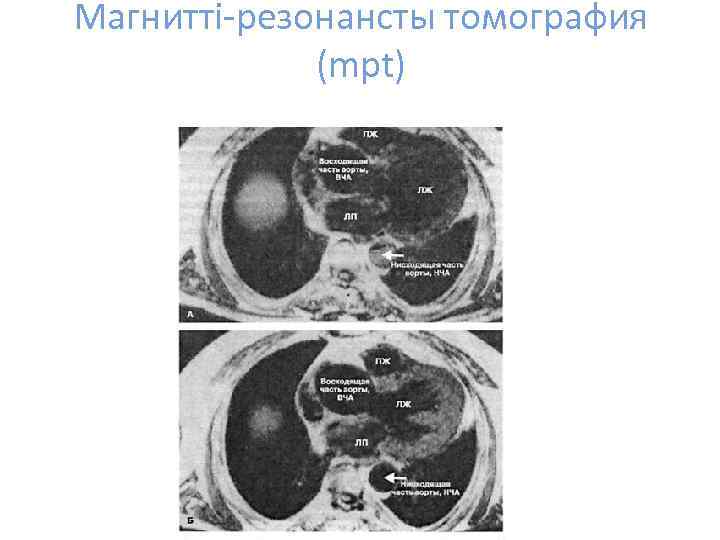

Магнитті-резонансты томография (mpt)